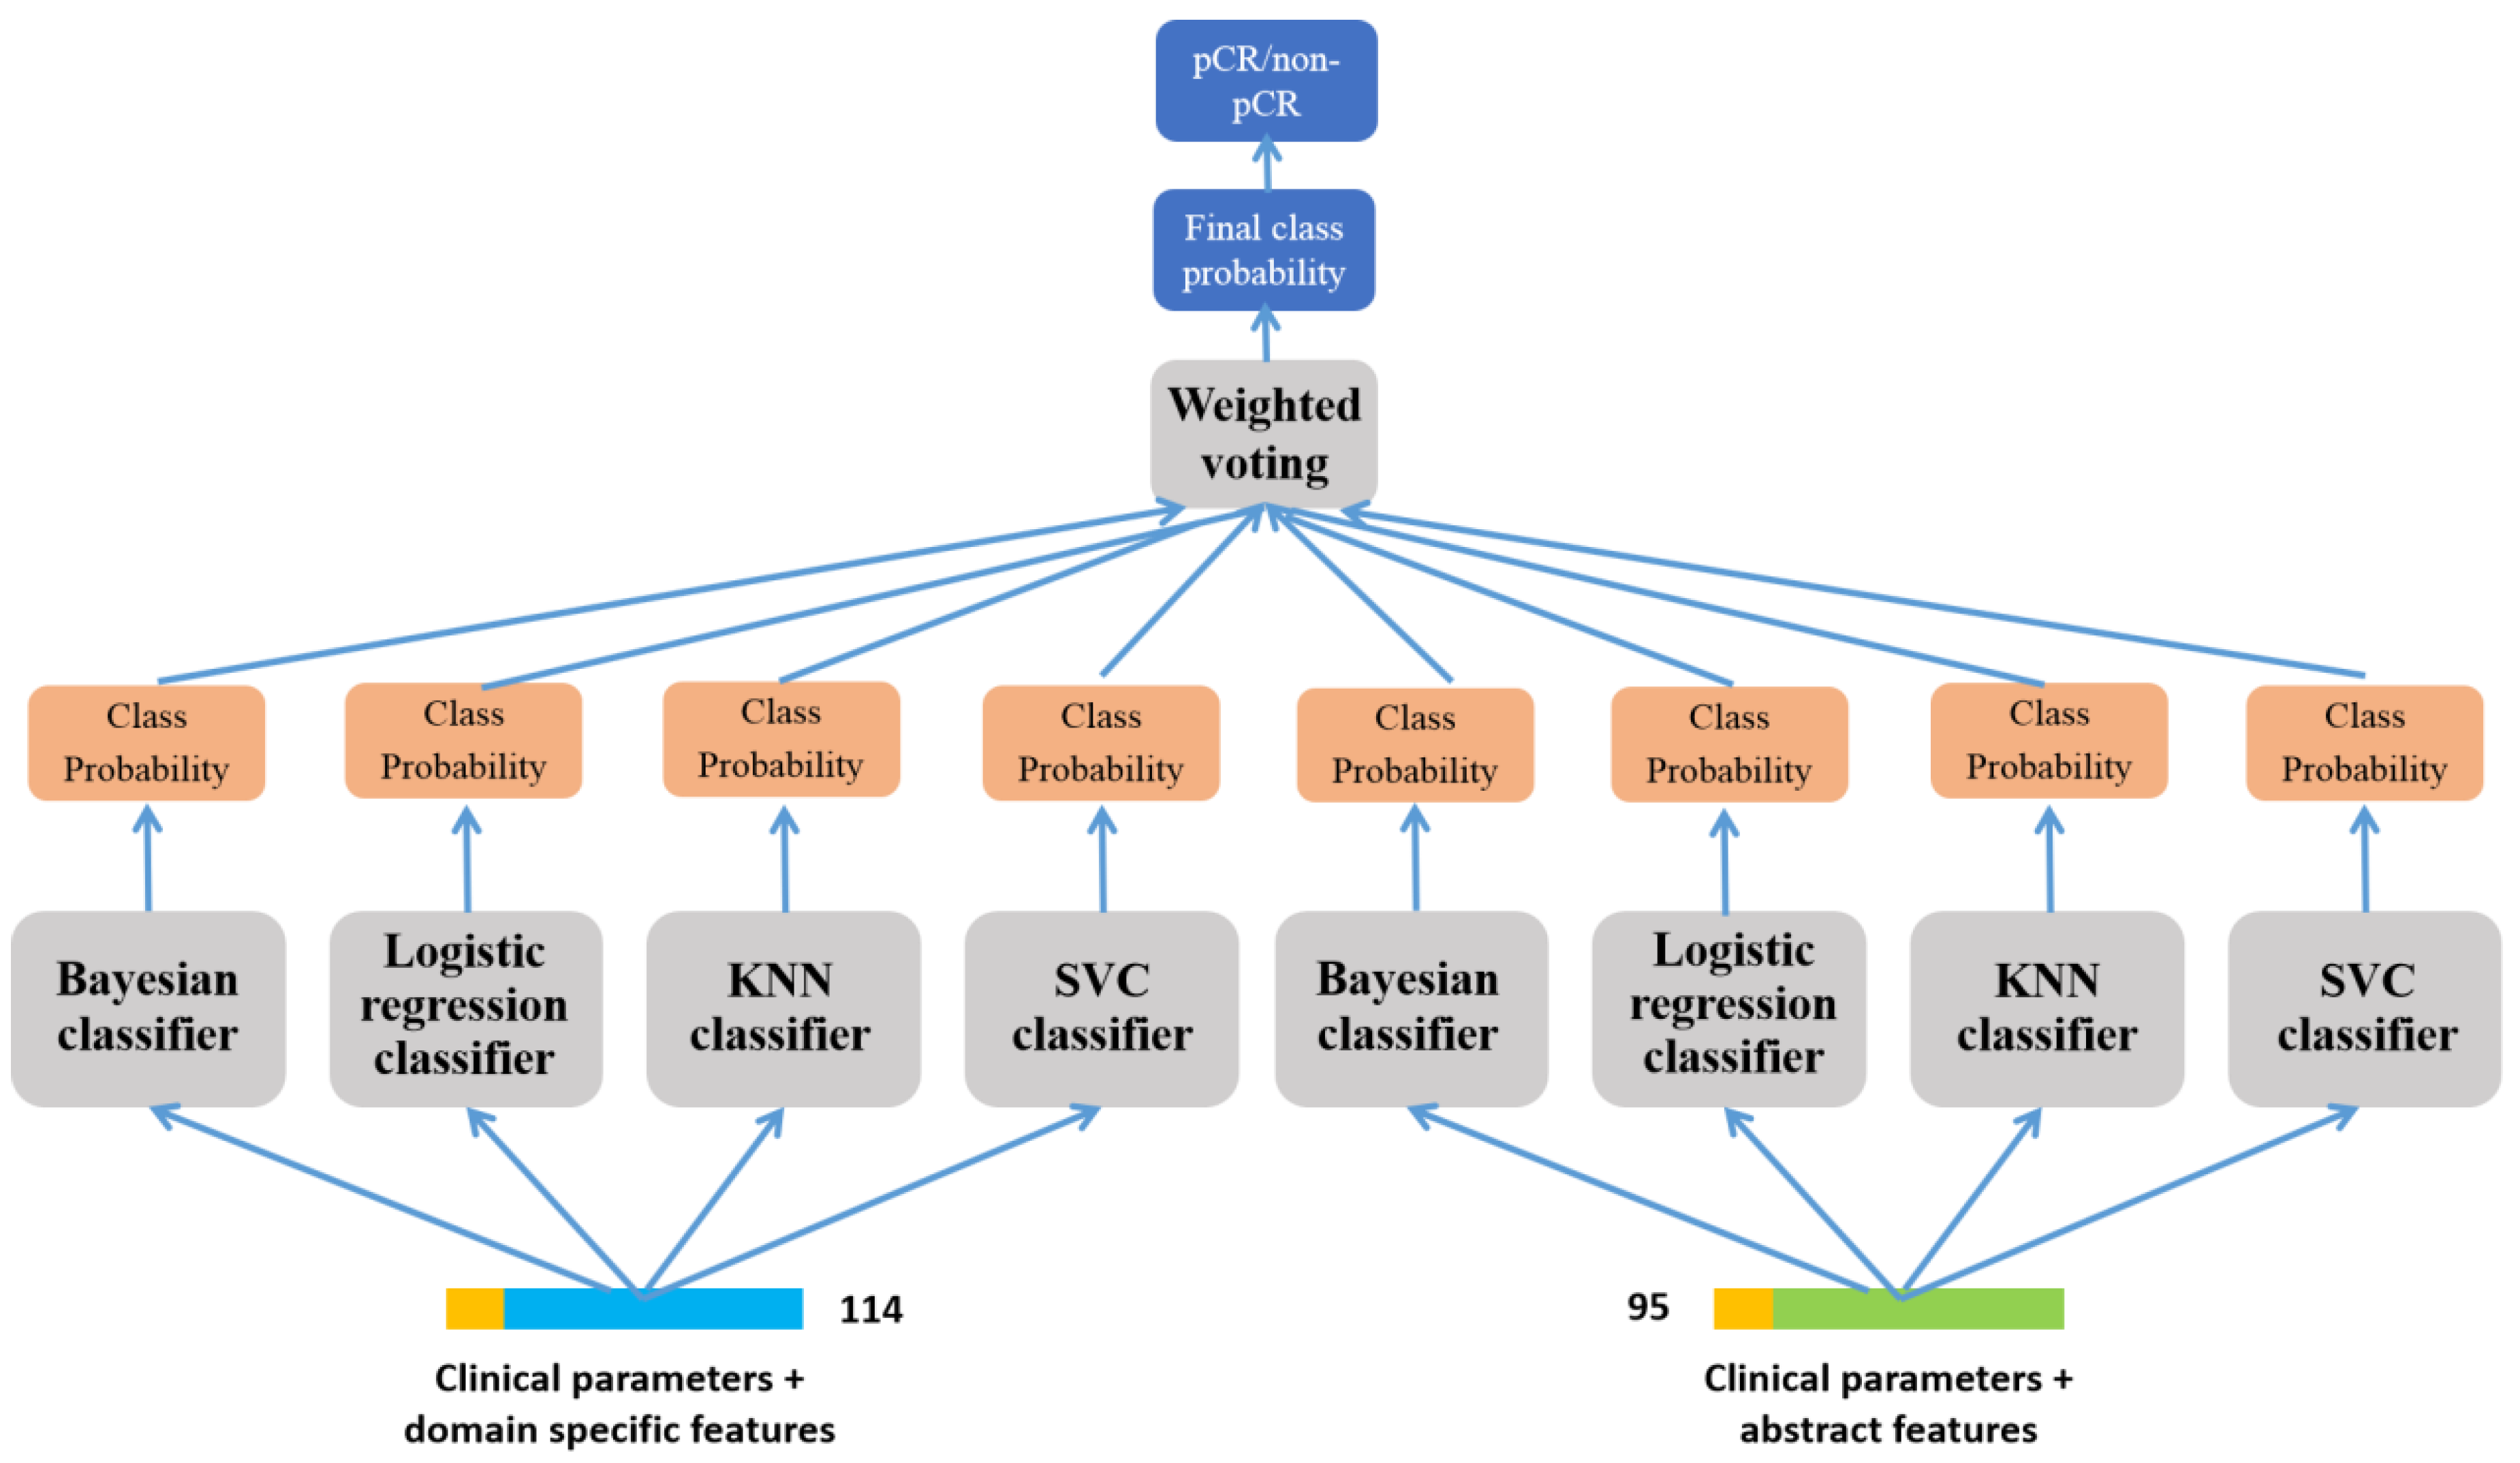

2.2.5. Prediction of pCR-Based on Ensemble Learning